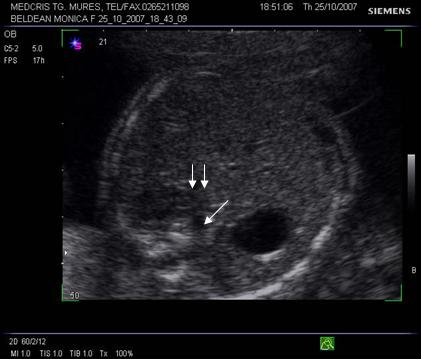

Fig. nr.177. Planul 1 de sectiune, cu imaginea de inima in 4 camere.